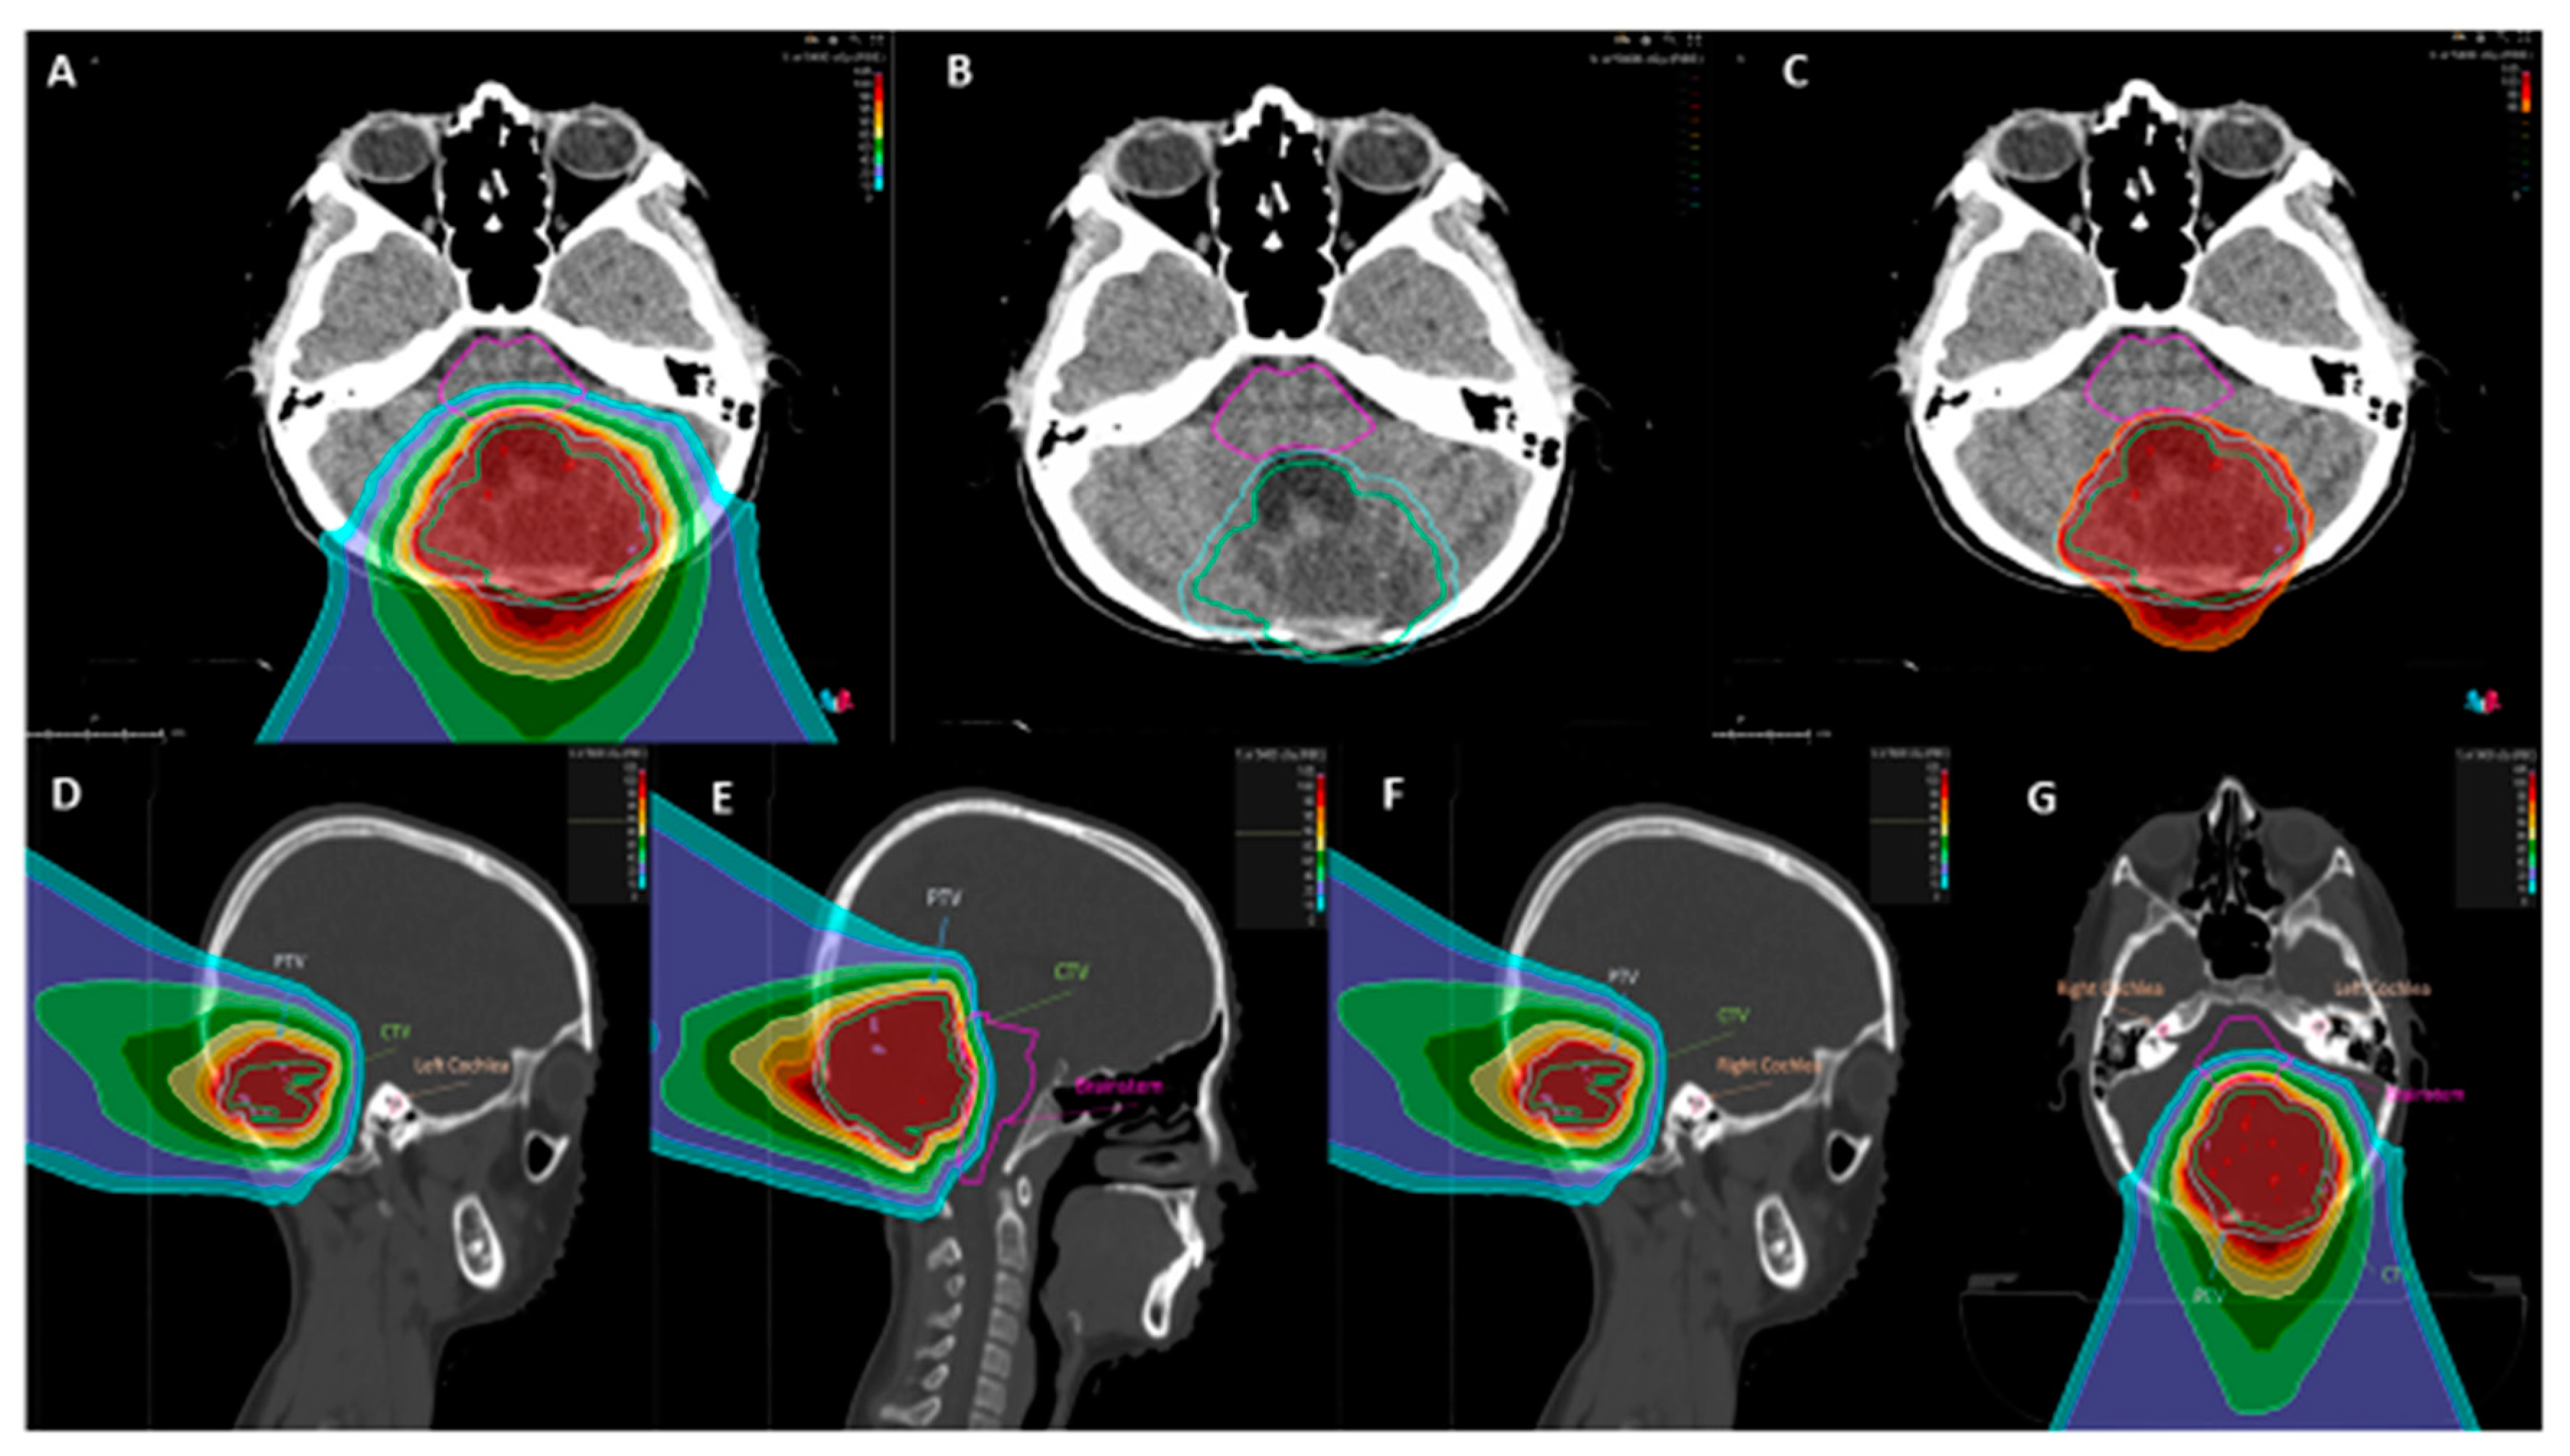

Eight months after the second surgery, an MRI documented a second recurrence at the local level (Figure 1L). The girl was therefore a candidate for proton therapy program (Figure 1M). The proton treatment was carried-out for one month (Figure 3A–C). Dose distributions of the 3-fields proton plan, optimized with single-field-optimization (SFO) technique to deliver 54 Gy relative biological effectiveness (RBE) in 30 fractions (1.8 Gy RBE per fraction).

Figure 3.

PBT: (A,G) axial dose distributions of the 3-fields proton plan. (B) The clinical target volume (CTV, in light green), the planning target volume (PTV, in light blue) and the brainstem (in purple) contoured are highlighted. (C) Reports a focus on the high dose region (>95% of the prescription dose), showing a high dose conformity to the target and homogeneity. Dose brain steam: 52.6 Gray (RBE) left and right cochlea: no dose; 0 Gray (RBE). (D–F): sagittal dose distribution of the 3-fields proton plan.